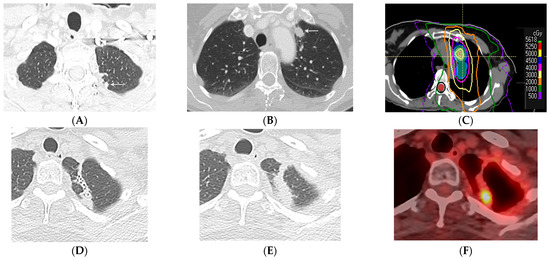

2.4. Stereotactic Body Radiotherapy

- Chassagnon, G.; Martini, K.; Giraud, P.; Revel, M.P. Radiological assessment after stereotactic body radiation of lung tumours. Cancer Radiother. 2020, 24, 379–387. [Google Scholar] [CrossRef]

- Al-Umairi, R.; Tarique, U.; Moineddin, R.; Jimenez-Juan, L.; Kha, L.C.; Cheung, P.; Oikonomou, A. CT patterns and serial CT Changes in lung Cancer patients post stereotactic body radiotherapy (SBRT). Cancer Imaging 2022, 22, 51. [Google Scholar] [CrossRef]